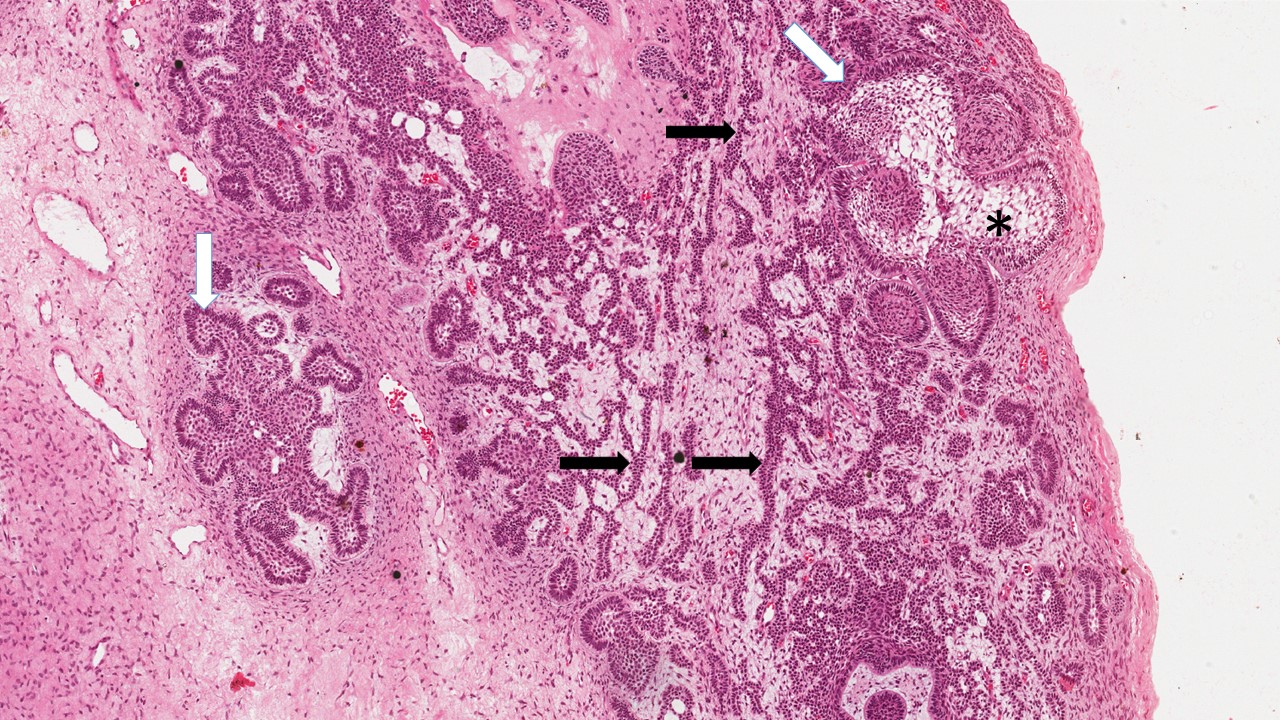

Descrição microscópica:

Ilhas de epitélio odontogênico entremeadas por estroma de tecido conjuntivo denso. As ilhas epiteliais consistem em uma região central de células arranjadas frouxamente, lembrando o retículo estrelado de um órgão do esmalte. Na periferia das ilhas nota-se camada de células colunares altas, semelhantes à pré-ameloblastos com núcleo hipercromático e polaridade invertida. Algumas ilhas apresentam metaplasia escamosa e/ou degeneração cística.

Dados importantes para o diagnóstico:

- Ilhas de tecido epitelial odontogênico (área demarcada);

- Células na periferia das ilhas, alongadas (em paliçadas) lembrando pré-ameloblastos (setas pretas);

- Células internas frouxamente arranjadas lembrando retículo estrelado (estrela);

- Tecido conjuntivo denso com aspecto de normalidade (asterisco);

- Metaplasia escamosa (triangulo);

- Degeneração cística (seta branca).